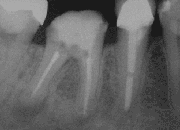

X-ray of a tooth after root end surgery

A root end surgery, also known as apicoectomy (apico- + -ectomy), apicectomy (apic- + -ectomy), retrograde root canal treatment (cf. orthograde root canal treatment) or root-end filling, is an endodontic surgical procedure whereby a tooth's root tip is removed and a root end cavity is prepared and filled with a biocompatible material. It is an example of a periradicular surgery.